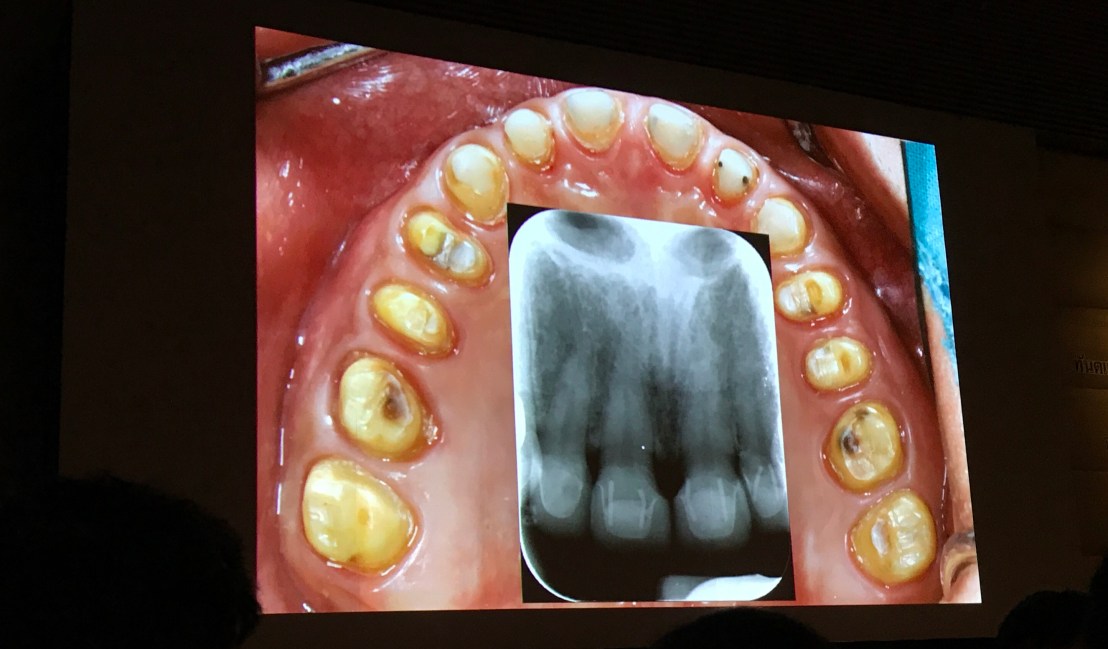

เคสที่ 3 คือ เคสที่ฟันสึกจากสาเหตุ Erosion

Wax up แบบฟันสึก แต่ไม่ loss VD ครับ

ใน case Erosion (ของผู้ป่วยหญิงเคสที่ 3) ท่านอาจารย์ได้แยก cause of pathology ออกมาให้ดู

เพราะ Erosion มีลักษณะที่เฉพาะต่างจาก pathologic attrition แบบอื่น

สังเกตในวงกลมสีเขียว inorganic part ของฟันไปหมดละครับจากกรด แต่ composite filling ยังคงอยู่แทบจะสมบูรณ์ ซึ่งเป็นลักษณะเฉพาะอย่างหนึ่ง

Intra-Oral